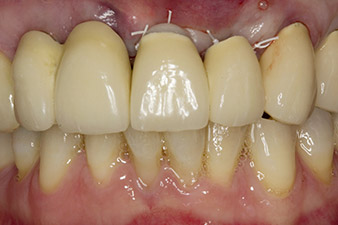

Fig. 6 : La situation après pose de l'implant et augmentation : L'ancien bridge a été remis en place en tant que restauration temporaire le temps de la cicatrisation, avec un pontique librement fraisé à la position d'implant 22. La restauration définitive prévue sera un bridge en oxyde de zirconium allant de la position 12 à l'implant qui reste à poser en position 23.